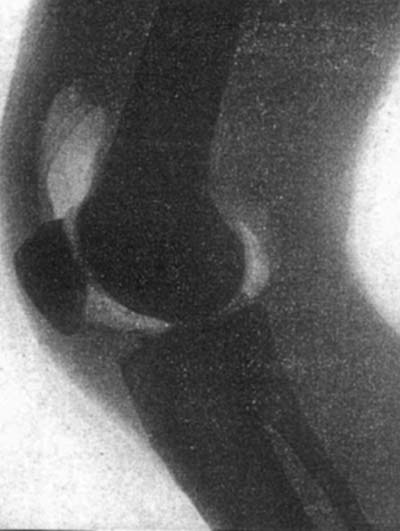

図9.酸素による膝関節造影.正常像[25].関節包はわかるが,半月板など膝内構造は良く見えない.

早くも1905年に膝関節に,陰性造影剤として酸素を注入する試みが学会報告され[24],翌1906年にもHoffaが酸素による膝関節造影を発表している[25](図9).しかし,軟骨や半月板と空気のコントラストには乏しく,また大量の酸素を注入することによる不快感,空気塞栓の危険などもあり,実用には至らなかった.1930年代になると,陽性造影剤であるヨード製剤が試みられ,さらに1933年にはBircherが空気を併用する二重造影を報告しているが[26],高浸透圧のイオン性造影剤は滑膜刺激,疼痛が強く,また余剰造影剤が垂れて関節構造が見えなくなる欠点があり普及しなかった.